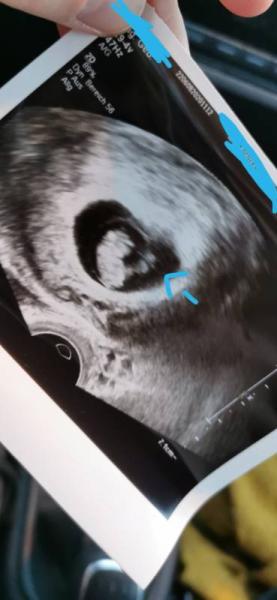

Hallöchen ihr lieben, kann mir jemand sagen was das markierte im Bild darstellt? Die Plazenta??? Nächster Termin ist jetzt an 01.12 bei 11+2 ich freue mich jetzt schon drauf das böhchen wieder zu sehen. Danke!

Erst vom dottersack würd ich sagen